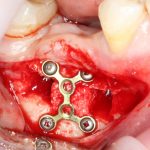

Я зафиксировал костный блок практически без адаптации на несколько винтов. Обрати внимание, что винты находятся в зоне, где не планируется установка имплантатов. Фиксация должна быть надежной, поскольку мне еще предстояла подготовка лунок для имплантатов. Трех винтов для этого вполне достаточно.

Напомню, что для этой работы я выбрал субкрестальные имплантаты Ankylos C/X. Они прекрасно сочетаются с любым методом остеопластики.

Глянем на то, что получилось:

Осталось адаптировать костный блок (убрать острые края), проверить его фиксацию и, при необходимости, добавить винты. Десятисекундное дело.